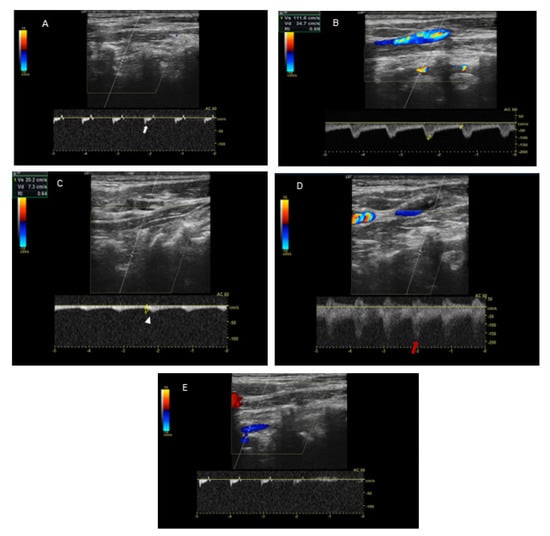

Because of the suspected dynamic stenosis, a dynamic CT angiography (D-CTA) of the carotid, vertebral and cerebral arteries was performed. Firstly, the imaging was conducted with the patient’s head in the neutral position. It revealed atheromatous plaques in both carotid bulbs (slightly calcified; maximum thickness: 2.8 mm) with no hemodynamically significant stenosis, grade 2 of kinking of R-ICA and a tortuosity of L-ICA. Furthermore, hypoplasia of R-VA was demonstrated (widths: R-VA 1.9 mm; L-VA 3.6 mm). L-VA had a tortuous course and it formed a loop at the level of the C4 vertebrae. There was no L-VA stenosis in this position (Figure 2A). Subsequently, D-CTA was acquired during left-side rotation of the head. In this examination the lumen of L-VA was narrowed up to 2 × 3.2 mm, causing 60% stenosis according to the NASCET criteria (Figure 2B) [7]. 3D reconstructions of this pathology were also obtained (Figure 3A,B). It was also observed that basilar artery (BA) was formed exclusively by L-VA. No abnormalities of other cerebral arteries were observed.

Figure 3. 3D reconstruction in the neutral head position and left-side head rotation. Panel (A): Coronal 3D reconstruction of the vertebral arteries in the neutral position of the head demonstrates L-VA loop in V2 segment at C4 level (yellow arrow) and R-VA hypoplasia (yellow arrowhead). No L-VA stenosis in this position. BA is formed exclusively by L-VA (red arrow). Panel (B): Coronal 3D reconstruction of the vertebral arteries in left-side head rotation demonstrates the narrowing of L-VA lumen (up to 2 mm × 3.2 mm) that causes a dynamic 60% L-VA stenosis in the loop at C4 level (yellow arrow).